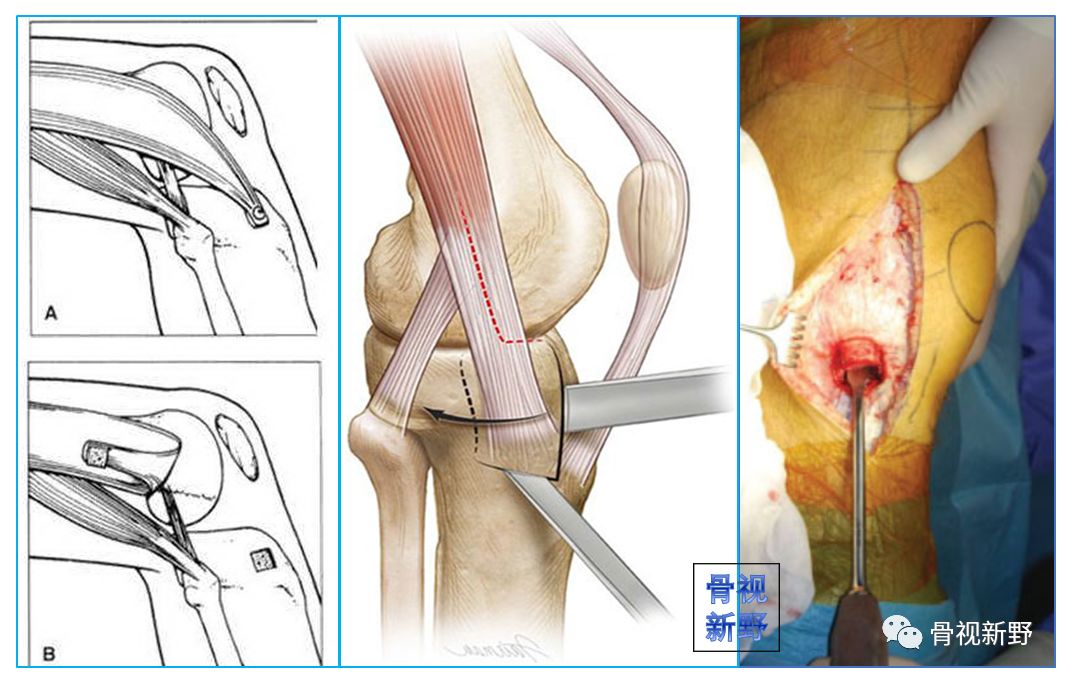

后外侧入路

适应症:II型外侧髁Hoffa骨折。操作:自髂胫束和股二头肌之间进入。

改良后外侧入路

适应症:II型外侧髁Hoffa骨折。

操作:自股骨外上髁至腓骨颈做一纵向切口,首先在腓骨颈远侧显露腓总神经,并向近侧游离,切开股二头肌肌腱(前)和腓总神经之间的深筋膜,股二头肌牵向外侧,腓总神经牵向内侧,显露后外侧关节囊,自远侧半月板附着部位向近侧纵向切开关节囊,在半月板位置的关节囊留置缝线,用以牵开关节囊显露股骨远端。

患者仰卧位,自股骨外上髁至腓骨颈做一纵向切口。

切开股二头肌肌腱(前)和腓总神经之间的深筋膜。

显露腓总神经,股二头肌牵向外侧,腓总神经牵向内侧。

复位和临时固定。